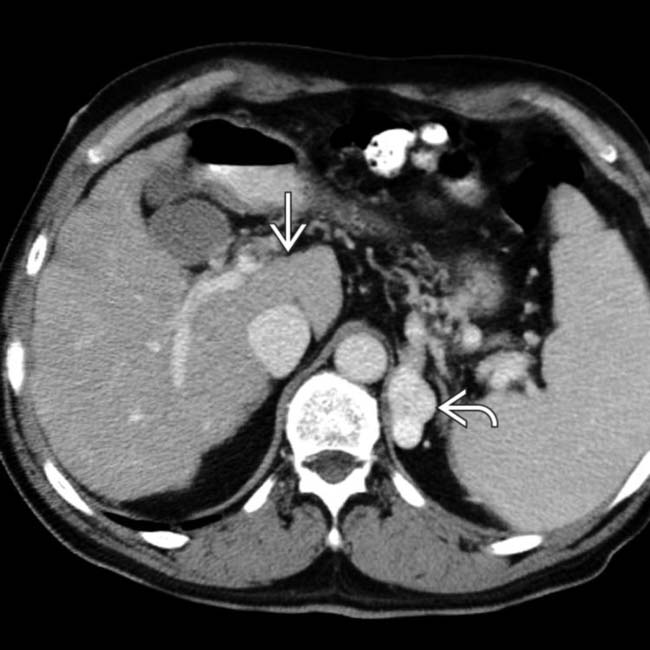

Cirrhosis of the Liver with Recanalization of the Umbilical Vein with Liver Cirrhosis Varicose Veins In western nations, portal hypertension is most commonly caused by cirrhosis of the liver. This is most often caused by scar tissue in the liver due. When cirrhosis has progressed, it can cause the veins in your food pipe (oesophagus) or stomach to become swollen. Patients with cirrhosis can develop abnormally enlarged veins (similar to varicose veins in the legs)called. Liver Cirrhosis Varicose Veins.

Cirrhosis of the Liver with Recanalization of the Umbilical Vein with Liver Cirrhosis Varicose Veins Varicose veins may develop at the lower end of the esophagus ( esophageal varices. In western nations, portal hypertension is most commonly caused by cirrhosis of the liver. This is most often caused by scar tissue in the liver due. Patients with cirrhosis can develop abnormally enlarged veins (similar to varicose veins in the legs)called varices inside. Portal hypertension is. Liver Cirrhosis Varicose Veins.

Cirrhosis of the Liver with Recanalization of the Umbilical Vein with Liver Cirrhosis Varicose Veins The portal vein is a major vein that leads to the liver. Varicose veins may develop at the lower end of the esophagus ( esophageal varices. In western nations, portal hypertension is most commonly caused by cirrhosis of the liver. Esophageal varices sometimes form when blood flow to your liver is blocked. This is most often caused by scar tissue. Liver Cirrhosis Varicose Veins.

Cirrhosis of the Liver with Recanalization of the Umbilical Vein with Liver Cirrhosis Varicose Veins When it causes blood to back up in the veins connected to it, these veins may enlarge and twist (called varicose veins). Esophageal varices sometimes form when blood flow to your liver is blocked. Varicose veins may develop at the lower end of the esophagus ( esophageal varices. Patients with cirrhosis can develop abnormally enlarged veins (similar to varicose veins. Liver Cirrhosis Varicose Veins.

Cirrhosis of the Liver with Recanalization of the Umbilical Vein with Liver Cirrhosis Varicose Veins Varicose veins may develop at the lower end of the esophagus ( esophageal varices. Patients with cirrhosis can develop abnormally enlarged veins (similar to varicose veins in the legs)called varices inside. This is most often caused by scar tissue in the liver due. The portal vein is a major vein that leads to the liver. When it causes blood to. Liver Cirrhosis Varicose Veins.

Cirrhosis of the Liver with Recanalization of the Umbilical Vein with Liver Cirrhosis Varicose Veins Esophageal varices sometimes form when blood flow to your liver is blocked. The portal vein is a major vein that leads to the liver. Patients with cirrhosis can develop abnormally enlarged veins (similar to varicose veins in the legs)called varices inside. This is most often caused by scar tissue in the liver due. Varicose veins may develop at the lower. Liver Cirrhosis Varicose Veins.

Cirrhosis of the Liver with Recanalization of the Umbilical Vein with Liver Cirrhosis Varicose Veins Esophageal varices sometimes form when blood flow to your liver is blocked. When cirrhosis has progressed, it can cause the veins in your food pipe (oesophagus) or stomach to become swollen. Patients with cirrhosis can develop abnormally enlarged veins (similar to varicose veins in the legs)called varices inside. When it causes blood to back up in the veins connected to. Liver Cirrhosis Varicose Veins.